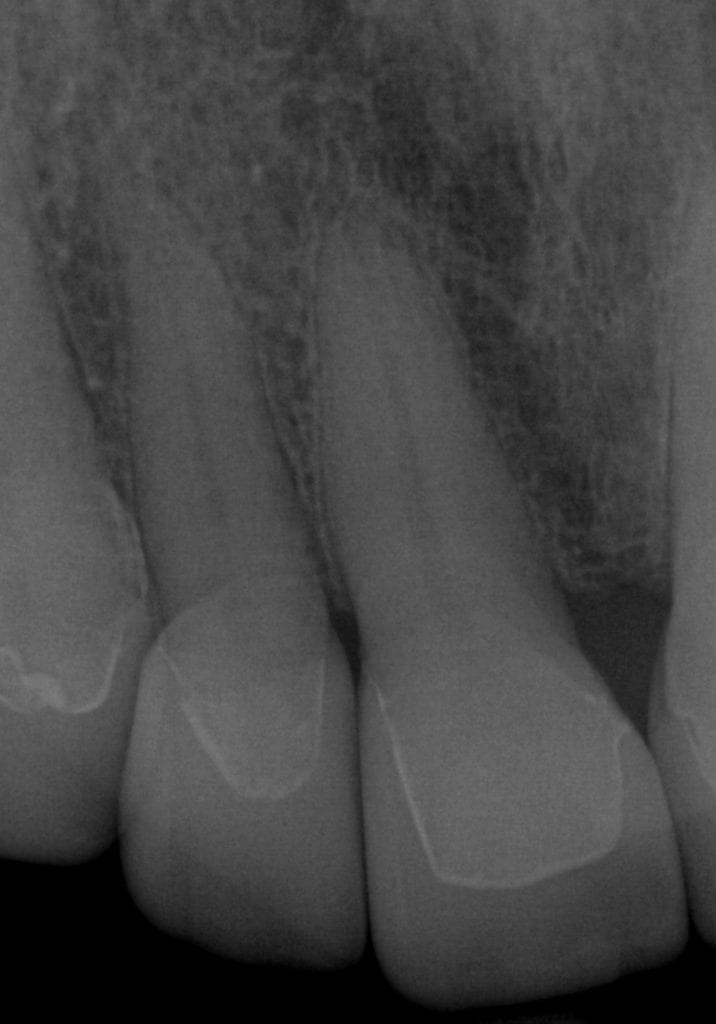

Pre-existing restorations that warranted replacement with an increase in vertical dimension.

Pre-existing restorations that warranted replacement with an increase in vertical dimension. The upper and lower arch were captured with the medit I500 and articulated together with enough clearance to accommodate new restorations and to restore the patient to an ideal tooth position.

ONE WEEK POST-OP RADIOGRAPHS / CEMENT CHECK